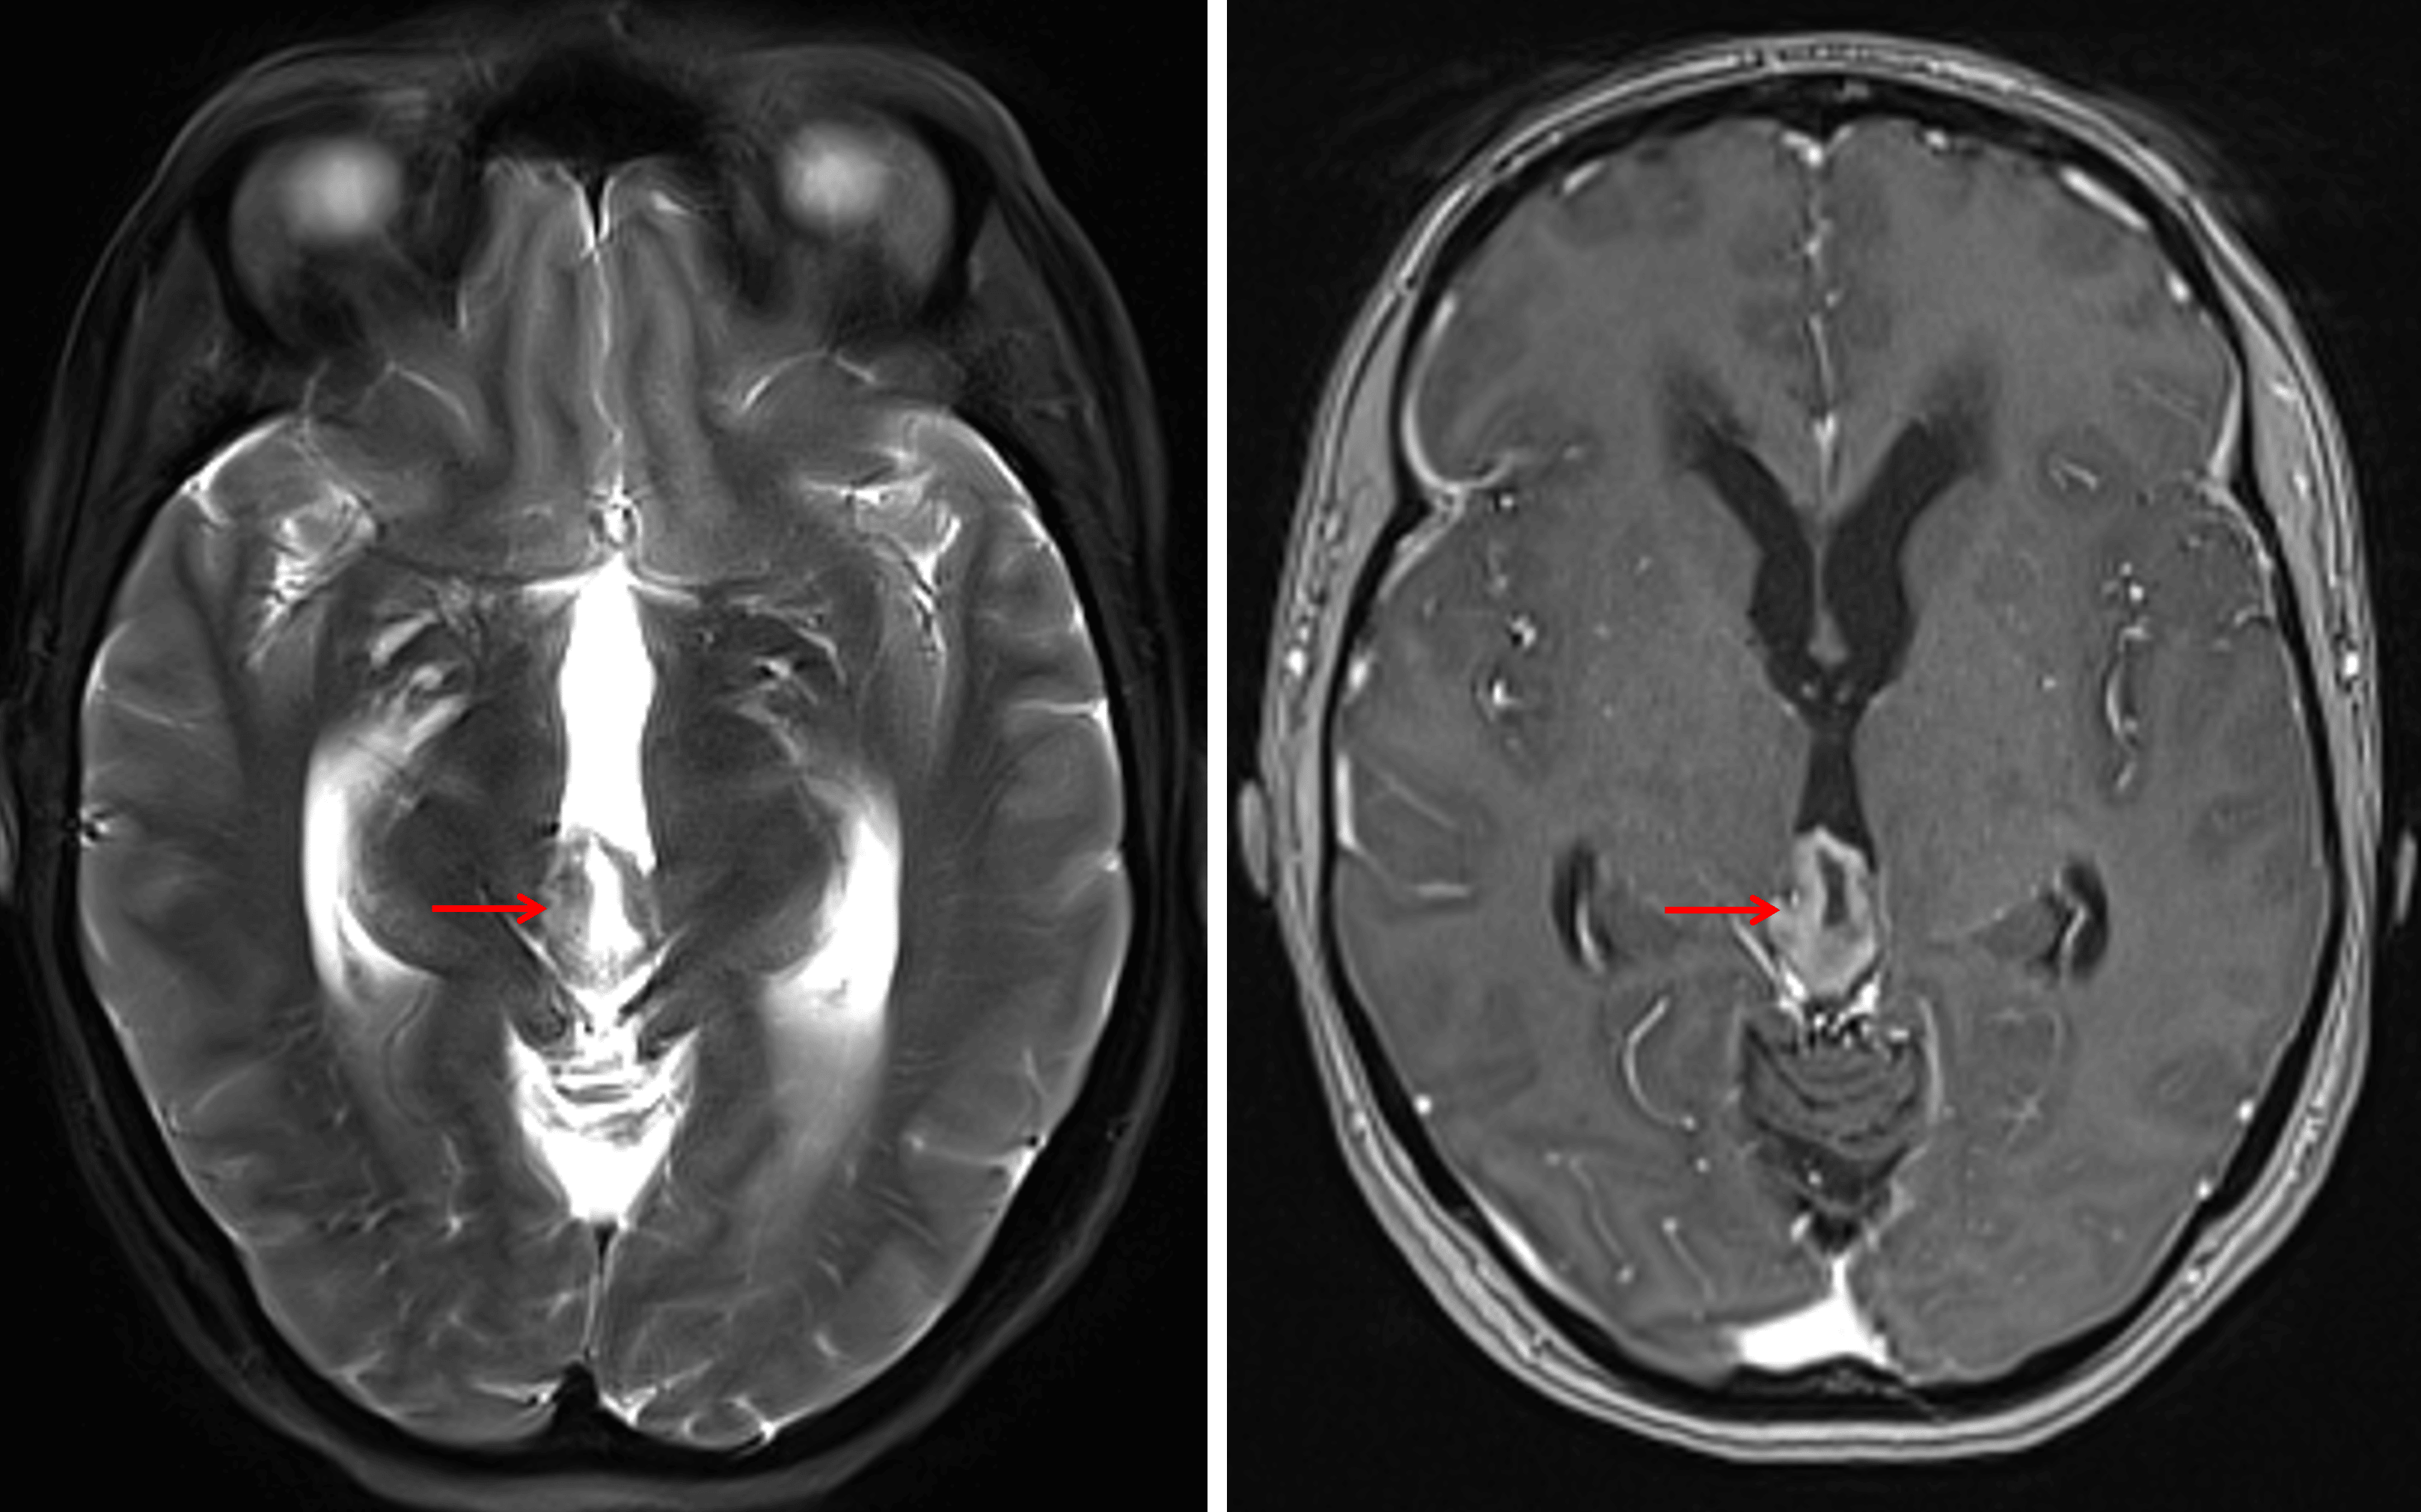

T1 hypointense pineal region mass (red arrow) with downward mass effect on the tectum and associated obstructive hydrocephalus.